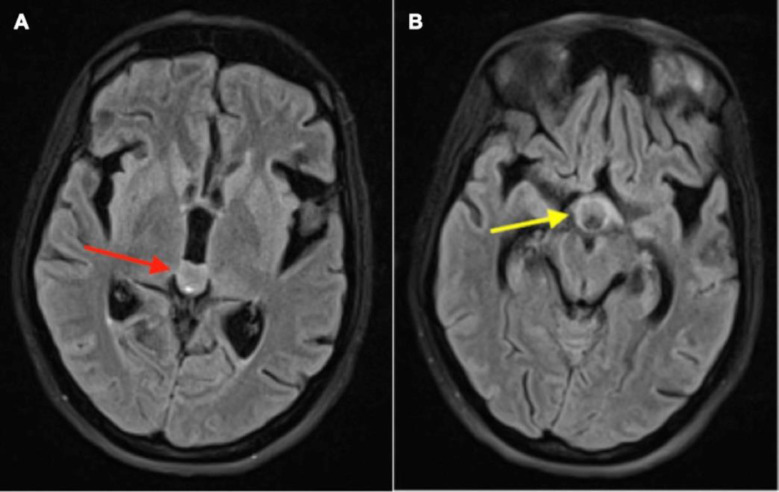

Pineal gland tumors are significant despite being rare (<1%) among all brain tumors. Germ cell tumors are the most common among the pineal gland tumors. Often affecting young adults, pineal gland germ cell tumors are hard to diagnose due to different symptoms and potential spread. But they rarely show leptomeningeal spread and extracranial metastases. Other differentials include primary tumors of the pineal region, Pineal gliomas, and metastases. The leptomeningeal spread of these tumors has not been studied so far. Conventional radiological imaging modalities are routinely used to diagnose and evaluate these tumors. We report a case here showing a pineal gland tumor with leptomeningeal spread detected by 18F-FDG PET/CT. Our case shows how pineal gland tumors can behave unusually and how 18F-FDG PET/CT can be crucial for accurately assessing the extent of the disease in the body to provide effective treatment. This case report illustrates the rare type of spread of pineal gland tumor and how 18F-FDG PET/CT helps detect this rare type of metastasis, thereby helping in prognostication and deciding further treatment of the patient.